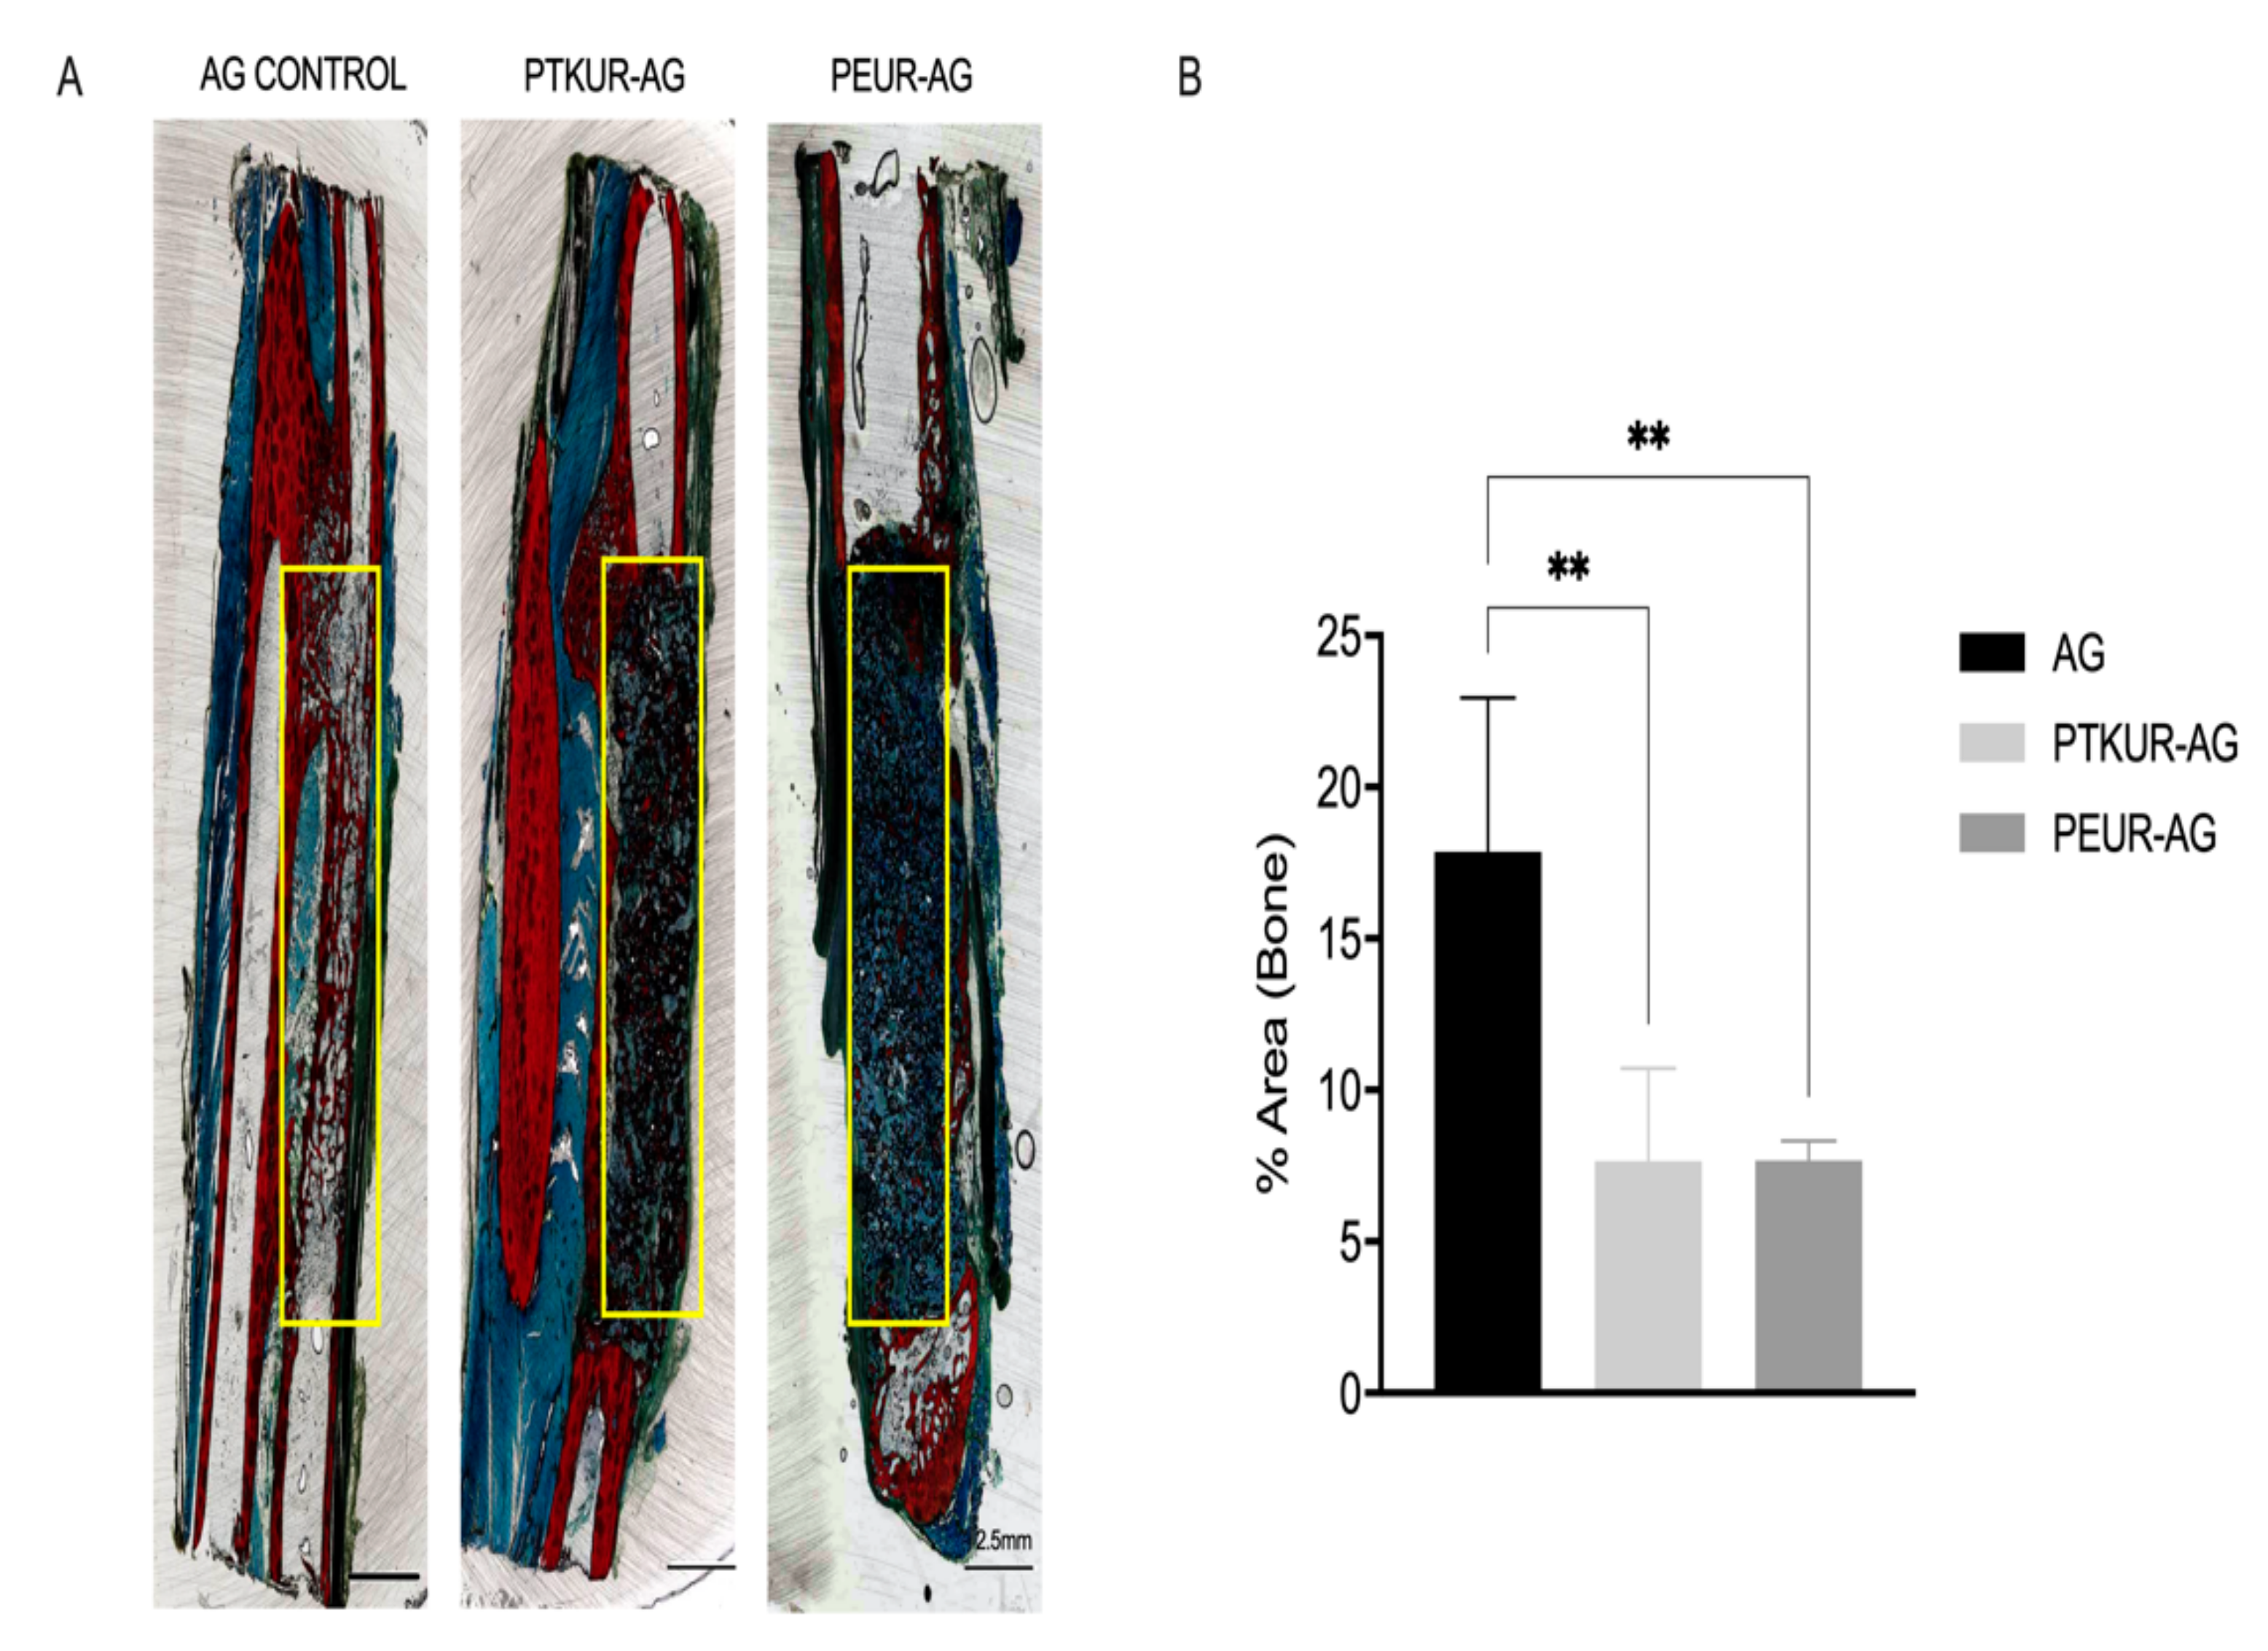

3.2. In Vivo Bone Analysis

3.3. PTKUR and PEUR Graft Remodeling